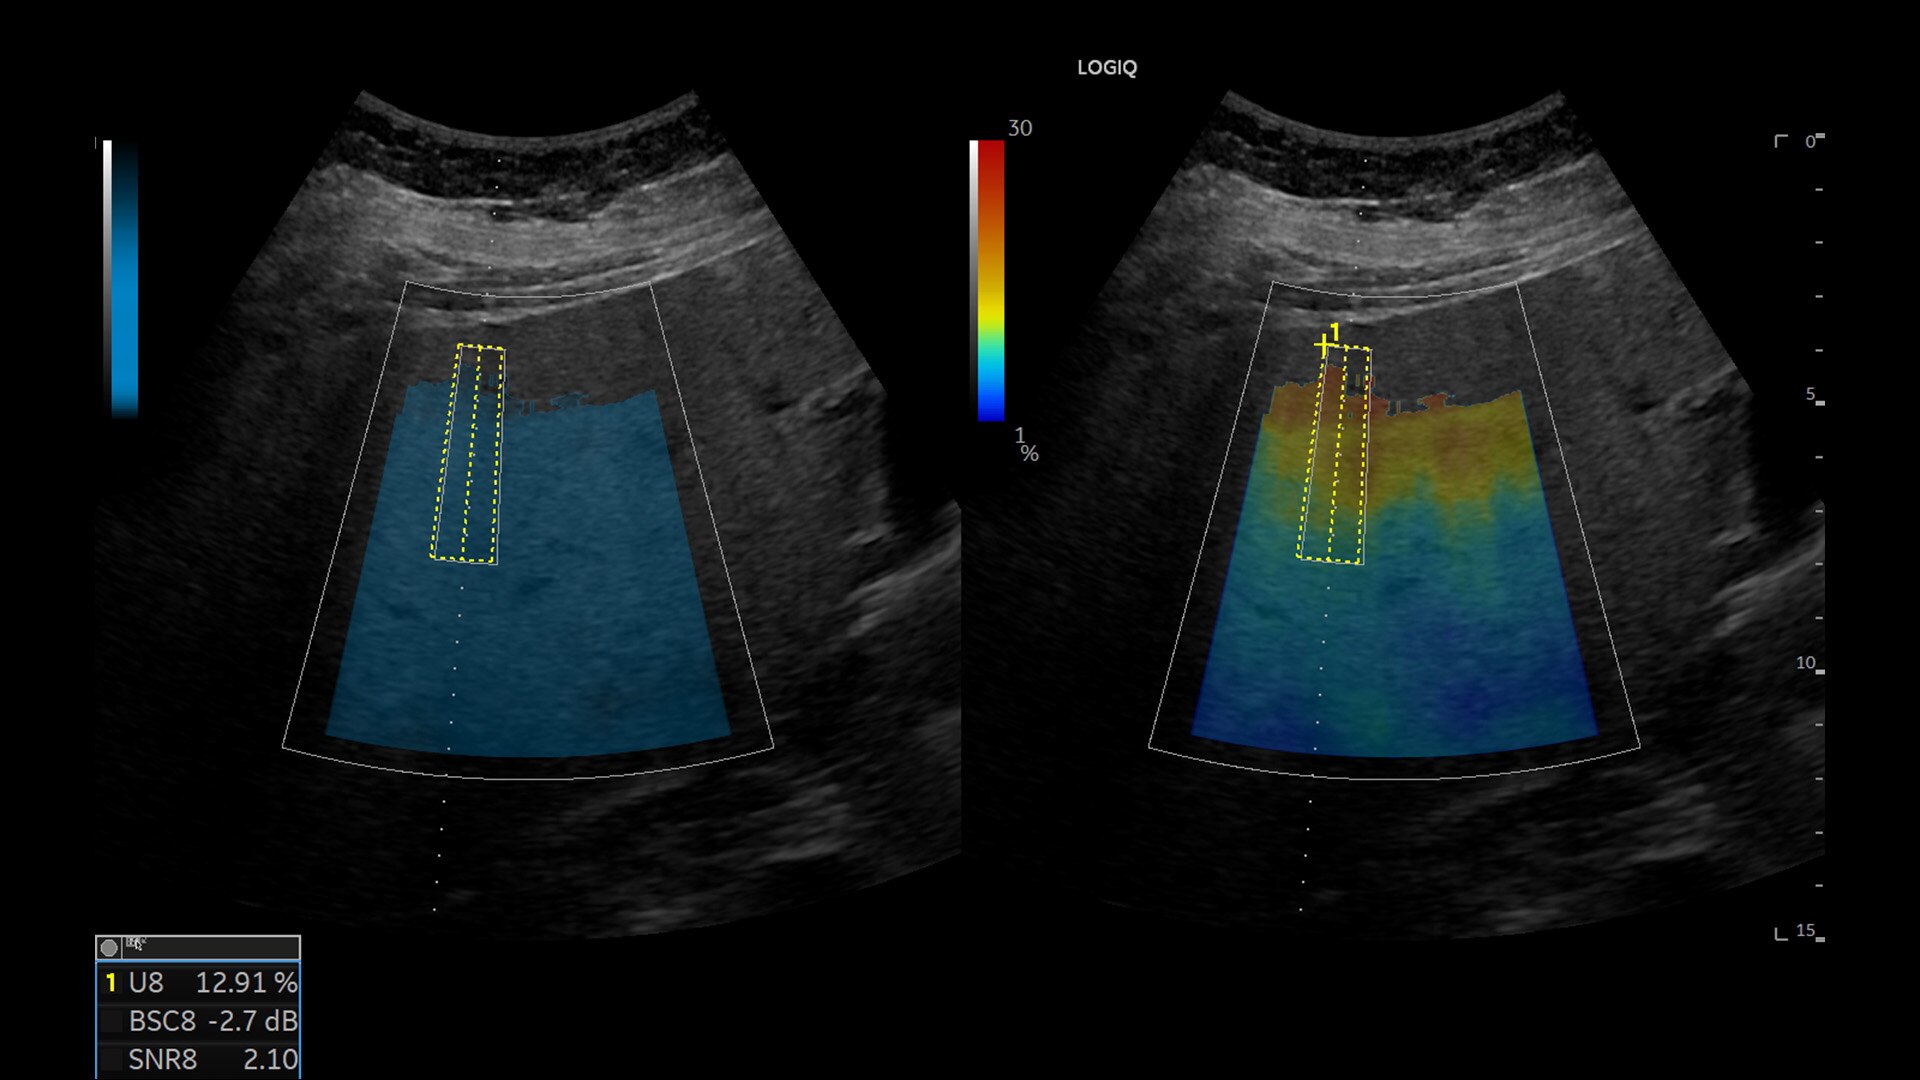

Radiologo NY Imaging, Stati Uniti

"Secondo i nostri specialisti in urologia, abbiamo finalmente il miglior marcatore delle lesioni e la massima qualità dell'immagine"